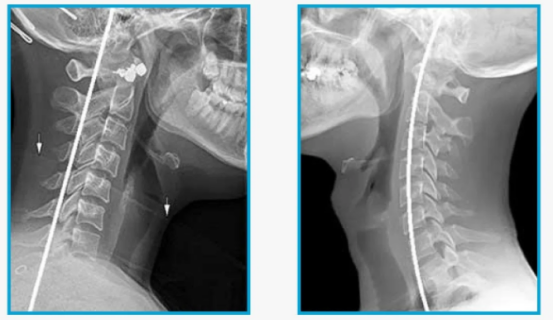

健康教育再不注意姿势,小心颈椎生理曲度变直了本文内容提要: 颈椎变直是怎么一回事。 颈椎变直有什么危害。 颈椎变直如何自我康复。 医院有什么项目可以加速颈椎生理曲度变直的恢复。 FunPT2023年3月24日